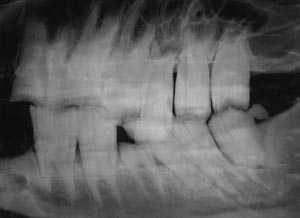

A common site for congenital anomalies of the digestive system is dentition. Many of these defects are present but not observable at birth so they are atypical congenital defects that don’t appear for months or several years after birth when various teeth erupt (or don’t erupt!). For this reason, the Kentucky study of congenital defects in foals does not list dental defects (AJVR 46: 353-358, 1985). Most equine veterinarians agree that dental defects are more common in smaller horses, especially miniature horses. Apparently, selection for small size resulted in a head too small for the teeth therein. In other words, it is easier to select for small bones than for small teeth. As a result, malocclusions can occur as some cheek teeth erupt and don’t have enough space to erupt into. Other common defects are polydontia (extra teeth) and oligodontia (missing teeth).